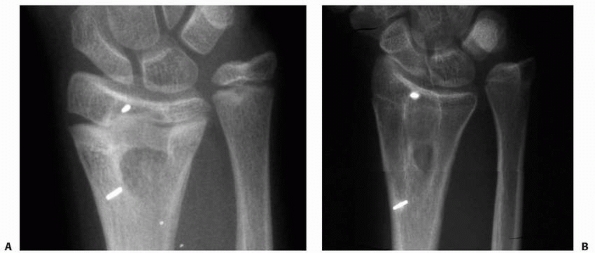

in the epiphysis and metaphysis at the time of arrest resection to

allow reasonably accurate estimation of the amount of longitudinal

growth that occurs across the operated physis, as well as to identify

the deceleration or cessation of that growth (Fig. 5-46).

We believe that precise monitoring of subsequent longitudinal growth is

an important aspect of the management of patients after arrest

resection. First, resumption of longitudinal growth may not occur

despite technically adequate arrest resection in patients with good

clinical indications. Perhaps more importantly, resumption of normal or

even accelerated longitudinal growth may be followed by late

deceleration or cessation of that growth.64

It is imperative that the treating surgeon be alert to those

developments, so that proper intervention can be instituted promptly.

Embedded metallic markers serve those purposes admirably.

| Figure 5-44 Fat used as an interposition material in partial physeal arrest resection can persist and hypertrophy during longitudinal growth. A. Radiograph appearance after traumatic distal radial physeal arrest resection. B. Appearance 5 years later. Longitudinal growth between the metallic markers is obvious. The fat-filled cavity created at physeal arrest resection has persisted and elongated with distal radial growth. |